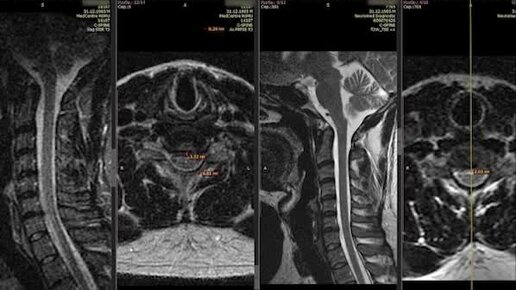

Результат лечения грыжи шейного отдела за 10 дней!